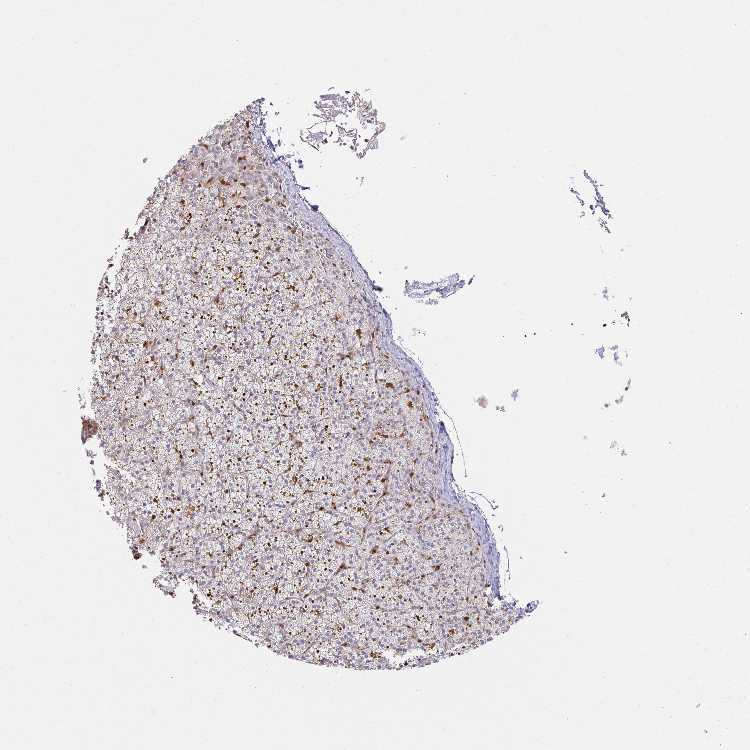

ADRENAL GLAND - Antibody stainingi

Antibody staining in the annotated cell types in the current human tissue is reported as not detected, low, medium, or high, based on conventional immunohistochemistry profiling in selected tissues. This score is based on the combination of the staining intensity and fraction of stained cells.

Each image is clickable and will lead to virtual microscopy that enables deeper exploration of all samples and also displays staining intensity scores, fraction scores and subcellular localization as well as patient and tissue information for each sample.

Antibody HPA049074Antibody HPA054496Antibody CAB006853Antibody CAB015948

Glandular cells Not detectedLowHighNot detected